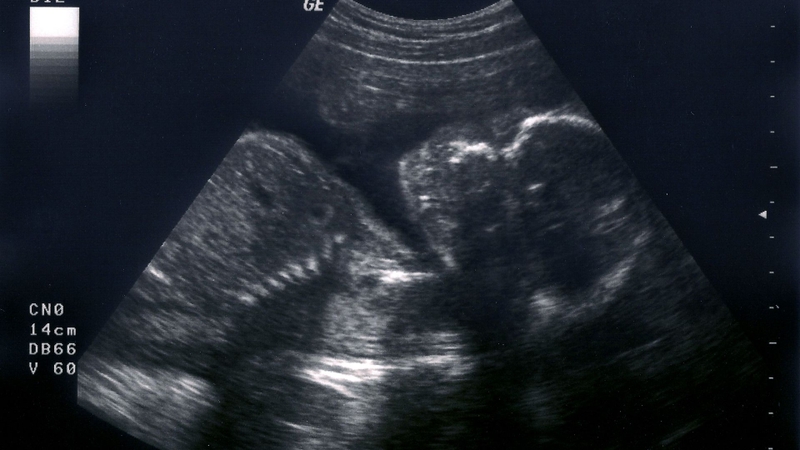

Tay và chân của thai nhi tuần 16 cũng phối hợp cử động nhịp nhàng hơn

Ở tuần thai thứ 16 (tính từ kỳ kinh cuối, tương đương khoảng 14 tuần sau thụ tinh), thai nhi có nhiều bước tiến rõ rệt về vận động và cấu trúc cơ thể. Các nhóm cơ vùng lưng và dọc cột sống phát triển mạnh hơn, giúp đầu và cổ bé giữ thẳng và linh hoạt hơn trước. Nhãn cầu đã có thể di chuyển nhẹ bên trong hốc mắt, trong khi tai tiếp tục hoàn thiện, những xương nhỏ trong tai dần đảm nhận chức năng dẫn truyền rung động, tạo nền tảng cho khả năng cảm nhận âm thanh từ môi trường bên ngoài.

Tay và chân của thai nhi cũng phối hợp cử động nhịp nhàng hơn, các động tác co duỗi có thể quan sát được qua siêu âm. Dù vậy, các chuyển động này vẫn còn rất nhẹ nên phần lớn mẹ bầu chưa cảm nhận rõ thai máy ở thời điểm này. Song song với sự phát triển của em bé, cơ thể mẹ cũng thay đổi đáng kể, trong đó vòng ngực thường tăng kích thước do tuyến vú tiếp tục phát triển để chuẩn bị cho quá trình tiết sữa sau sinh.